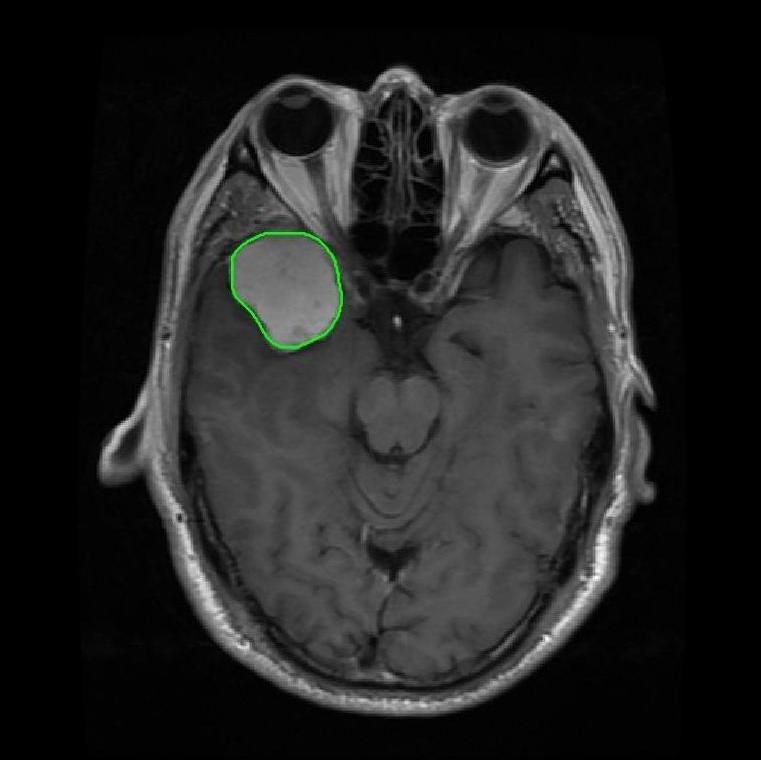

From the above discussions, we have discovered the significant potential of applying Retinex theory to image segmentation and explored its fundamental differences from traditional models. Traditional image segmentation models typically focus on the impact of intensity information on the segmentation results. Therefore, when faced with complex segmentation scenarios, the segmentation results are often affected by lighting, artifacts, and unclear boundaries in the image. As shown in Fig. 1, we present the results of the classical local model LIF [ZHANG20101199] for segmenting brain tumor images along with surrounding tissue edema. The irregular ring-like enhancement caused by the edematous tissue leads to irregular boundaries and low contrast in the images. Consequently, the LIF model can only identify the central necrotic and liquefied regions of the tumor, failing to detect the boundaries and becoming trapped in local minima. In this paper, we draw inspiration from the Retinex theory, which is widely applied in the field of image enhancement. According to Retinex theory, the reflectance component characterizes the intrinsic structural properties of the observed image and preserves texture information independent of illumination variations. By integrating this reflectance component into the level set framework, our model achieves robust segmentation of medical images even under severe intensity inhomogeneity. In addition, a linearized Structural-Prior is proposed to restore intensity consistency and capture local geometric features, thereby improving boundary localization in complex or blurred regions. Furthermore, a relaxed binary level set representation is employed to enhance robustness against noise and to enable accurate tracking of complex contours. Based on these innovations, we propose a novel variational reflectance-based level set model (RefLSM) that simultaneously corrects bias fields and performs segmentation. Experimental results demonstrate that RefLSM significantly outperforms conventional level set methods in both segmentation accuracy and robustness. We present the results of our model segmenting the two brain tumor images mentioned above in Fig. 2.

To address the challenge of segmenting images with severe intensity inhomogeneity, we propose a linearized structural prior that directly operates on the reflectance component . Reflectance-based structural information is more robust to illumination variations and bias field distortions, helping preserve weak edges and subtle anatomical boundaries. As shown in Fig. 2, our method can accurately delineate tumor boundaries and surrounding edema even under severe inhomogeneity, where traditional intensity-based models often fail. The proposed prior aligns smoothed reflectance gradients with data-driven directions, enhancing inter-region contrast, preserving weak edges, and stabilizing the evolution of . Formally, we define the linear structure operator as the gradient field of the smoothed reflectance: